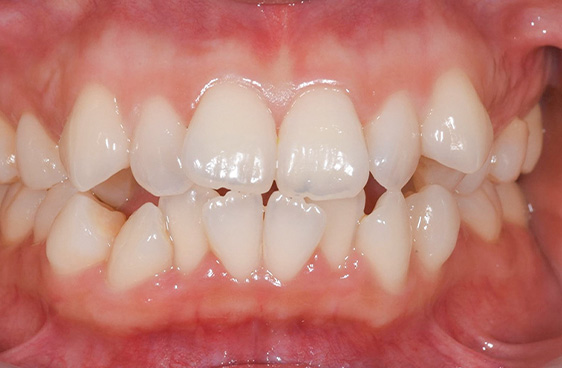

- 症例1

治療期間 約8カ月

治療費 23.1万円(税込)